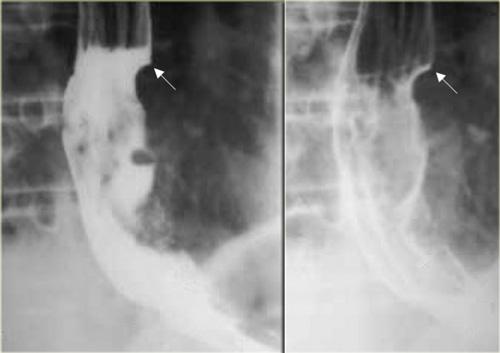

Achalasia cơ nhẫn hầu ở phụ nữ 46 tuổi. Cảm giác có khối vướng ở cổ họng. Ấn lõm dai dẳng (mũi tên) do cơ nhẫn hầu không giãn ra khi khối thức ăn di chuyển xuống phía dưới

Cơ thắt thực quản trên

- Được tạo thành chủ yếu bởi cơ nhẫn hầu.

- Nằm ở mức C5-C6

- Bình thường giãn ra khi có khối thức ăn đi qua

- Các bất thường

- Giãn chậm

- Đóng sớm

- Không giãn: có hoặc không có triệu chứng; nếu có triệu chứng, được gọi là achalasia cơ nhẫn hầu